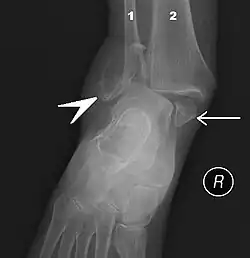

Der Knöchel bildet die Gelenkpfanne des Sprunggelenkes aus. Das untere Ende des Wadenbeins bildet den tiefer herabreichenden Außenknöchel (lateinisch-anatomisch Malleolus lateralis (fibulae)), das untere Ende des Schienbeines den Innenknöchel (lateinisch-anatomisch Malleolus medialis (tibiae)).

Der Knöchelbruch (fachsprachlich auch Malleolarfraktur) ist eine der häufigsten Sportverletzungen. 40 Prozent dieser Verletzungen sind sportbedingt. Der Bruch des Innenknöchels kommt häufiger vor als der des Außenknöchels, es können jedoch auch beide Knöchel gleichzeitig brechen (Bimalleolarfraktur). Knöchelbrüche treten fast immer zusammen mit Bänderrissen auf.

Beim dreifachen Knöchelbruch (lateinisch Trimalleolarfraktur) wird zusätzlich das vordere oder hintere untere Ende des Schienbeins ausgerissen, was als vorderes Volkmann-Dreieck bzw. hinteres Volkmann-Dreieck bezeichnet wird. Beim Volkmann’schen Dreieck handelt es sich um die Bezeichnung für den Bruch und nicht die gebrochene anatomische Struktur am vorderen oder hinteren unteren Ende des Schienbeins (hintere Schienbeinkante).